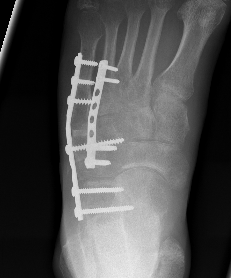

ORIF

Bridge plating

Cuboid plates

Severe comminution / lateral column shortening

- consider temporary distractor / external fixation to obtain length

- calcaneum to 4th / 5th metatarsal plate

- non-weight bearing until union then remove plates (typically 12 weeks)